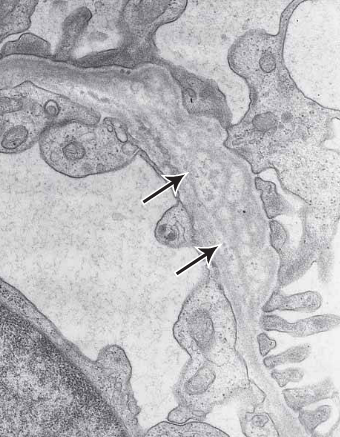

EM shows numerous subepithelial humps (arrows) and mesangial hypercellularity (arrowheads). Capillary lumina (L) are markedly narrowed

acute post infectious glomerulonephritis